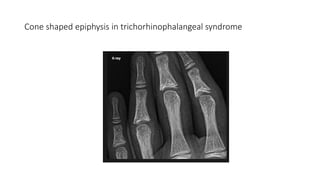

Cone shaped epiphysis in trichorhinophalangeal syndrome

Cone shaped epiphysisin trichorhinophalangeal syndrome